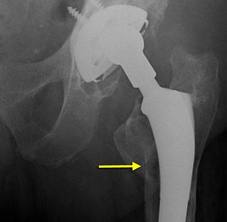

Osteolysis is a problem that causes the bone surrounding the implant to seemingly ‘melt away’. The weakening of bone around the hip replacement is seen on x-rays, and looks as though there are holes in the bone around the joint replacement. Because of the weakened bone, the hip replacement become loose, and begins to wobble within the bone. Patients experience symptoms of pain and limitations in motion of the hip. The technical name for this weakening of bone is called osteolysis.

In years past, this problem of holes in the bone seen on x-ray was called ‘cement disease’. This name comes from the fact that initially doctors did not know the cause of the weakening of bone. Because cement was used in the hip replacements, the problem was wrongly assumed to be due to the cement, thus the name cement disease. The name stuck, although it is now known that the cement is not the problem.

Osteolysis occurs as a result of wearing out of the parts of the hip replacement. Over years of use, microscopic fragments of the hip replacement cause irritation to the tissues around the implant, and begin to cause the weakening of bone. Even though modern hip replacements are made of materials that can withstand wearing out very well, even small amounts of these microscopic particles can damage the bone around the hip replacement.